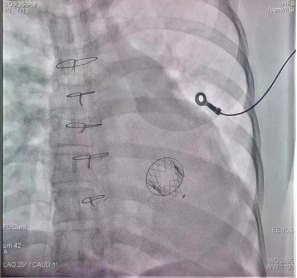

心尖导管二尖瓣“瓣中瓣”置换成功后的胸部X线